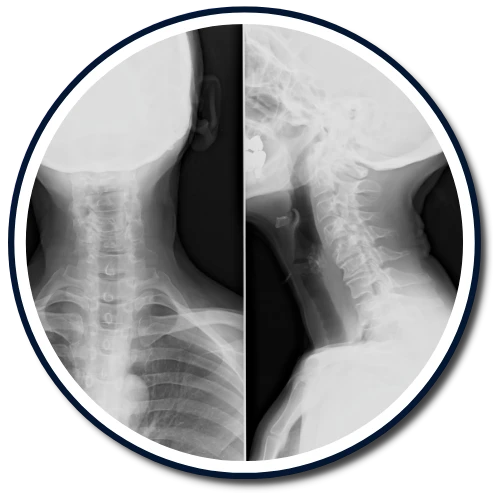

The Gonstead Technique relies on five essential components: Visualization, Instrumentation, Palpation, X-Ray, and patient symptoms. By integrating these elements, we can pinpoint the precise location that requires adjustment. When all these factors align, we can provide the patient with a specific and effective adjustment. Specificity is the key, as Dr. Gonstead emphasized that three adjustments on the wrong vertebral segment could lead to a Subluxation, highlighting the importance of precision.

According to the Gonstead methodology, understanding that subluxations originate from the disc is crucial. Recognizing the stages of disc degeneration is essential for determining the appropriate adjustment direction and force needed for effective correction.

Dr. Gonstead's Level Disc Theory asserts that "anatomically and physiologically normal discs promote optimum vertebral alignment." This is evidenced when the vertical height of a vertebral couple is uniform around 360 degrees, with the vertebral bodies properly aligned. This alignment, known as "Parallel Discs," ensures even weight distribution, adequate nutrient flow, and optimal joint function and movement within the spine.